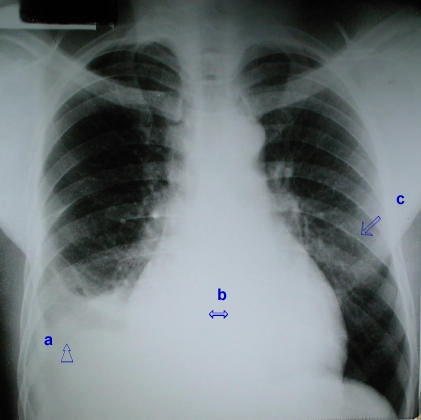

• Rx Tórax PA, Diagnóstico de taponamiento cardíaco

Rx Tórax PA. 12 días mas tarde.

- (a) - Derrame pleural derecho.

Radiopacidad basal derecha homogénea de concavidad superior, que borra el hemidiafragma, el seno costofrénico derecho, anterior y el cardiofrénico.

- (b) - Derrame pericárdico.

Aumento del diametro trasverso de la silueta cardíaca con aspecto de bota.

- (c) - Hipertensión arterial pulmonar.

Radiopacidad parahilear bilateral, de aspecto trabecular de origen vascular